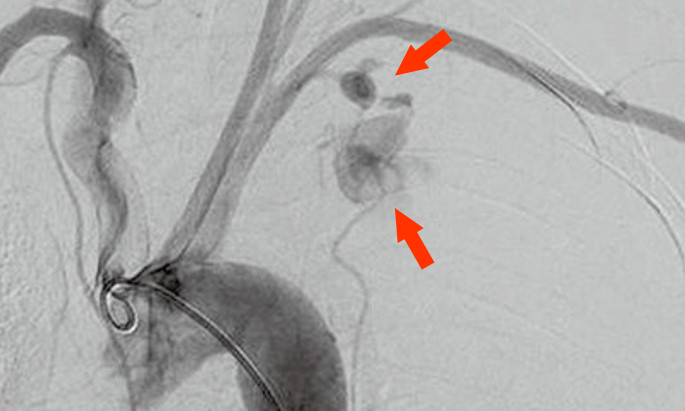

NF-1参考症例 31歳女性

• 腹痛、ショック

• SMAに2つの瘤、破裂の疑い

• カバードステントで止血